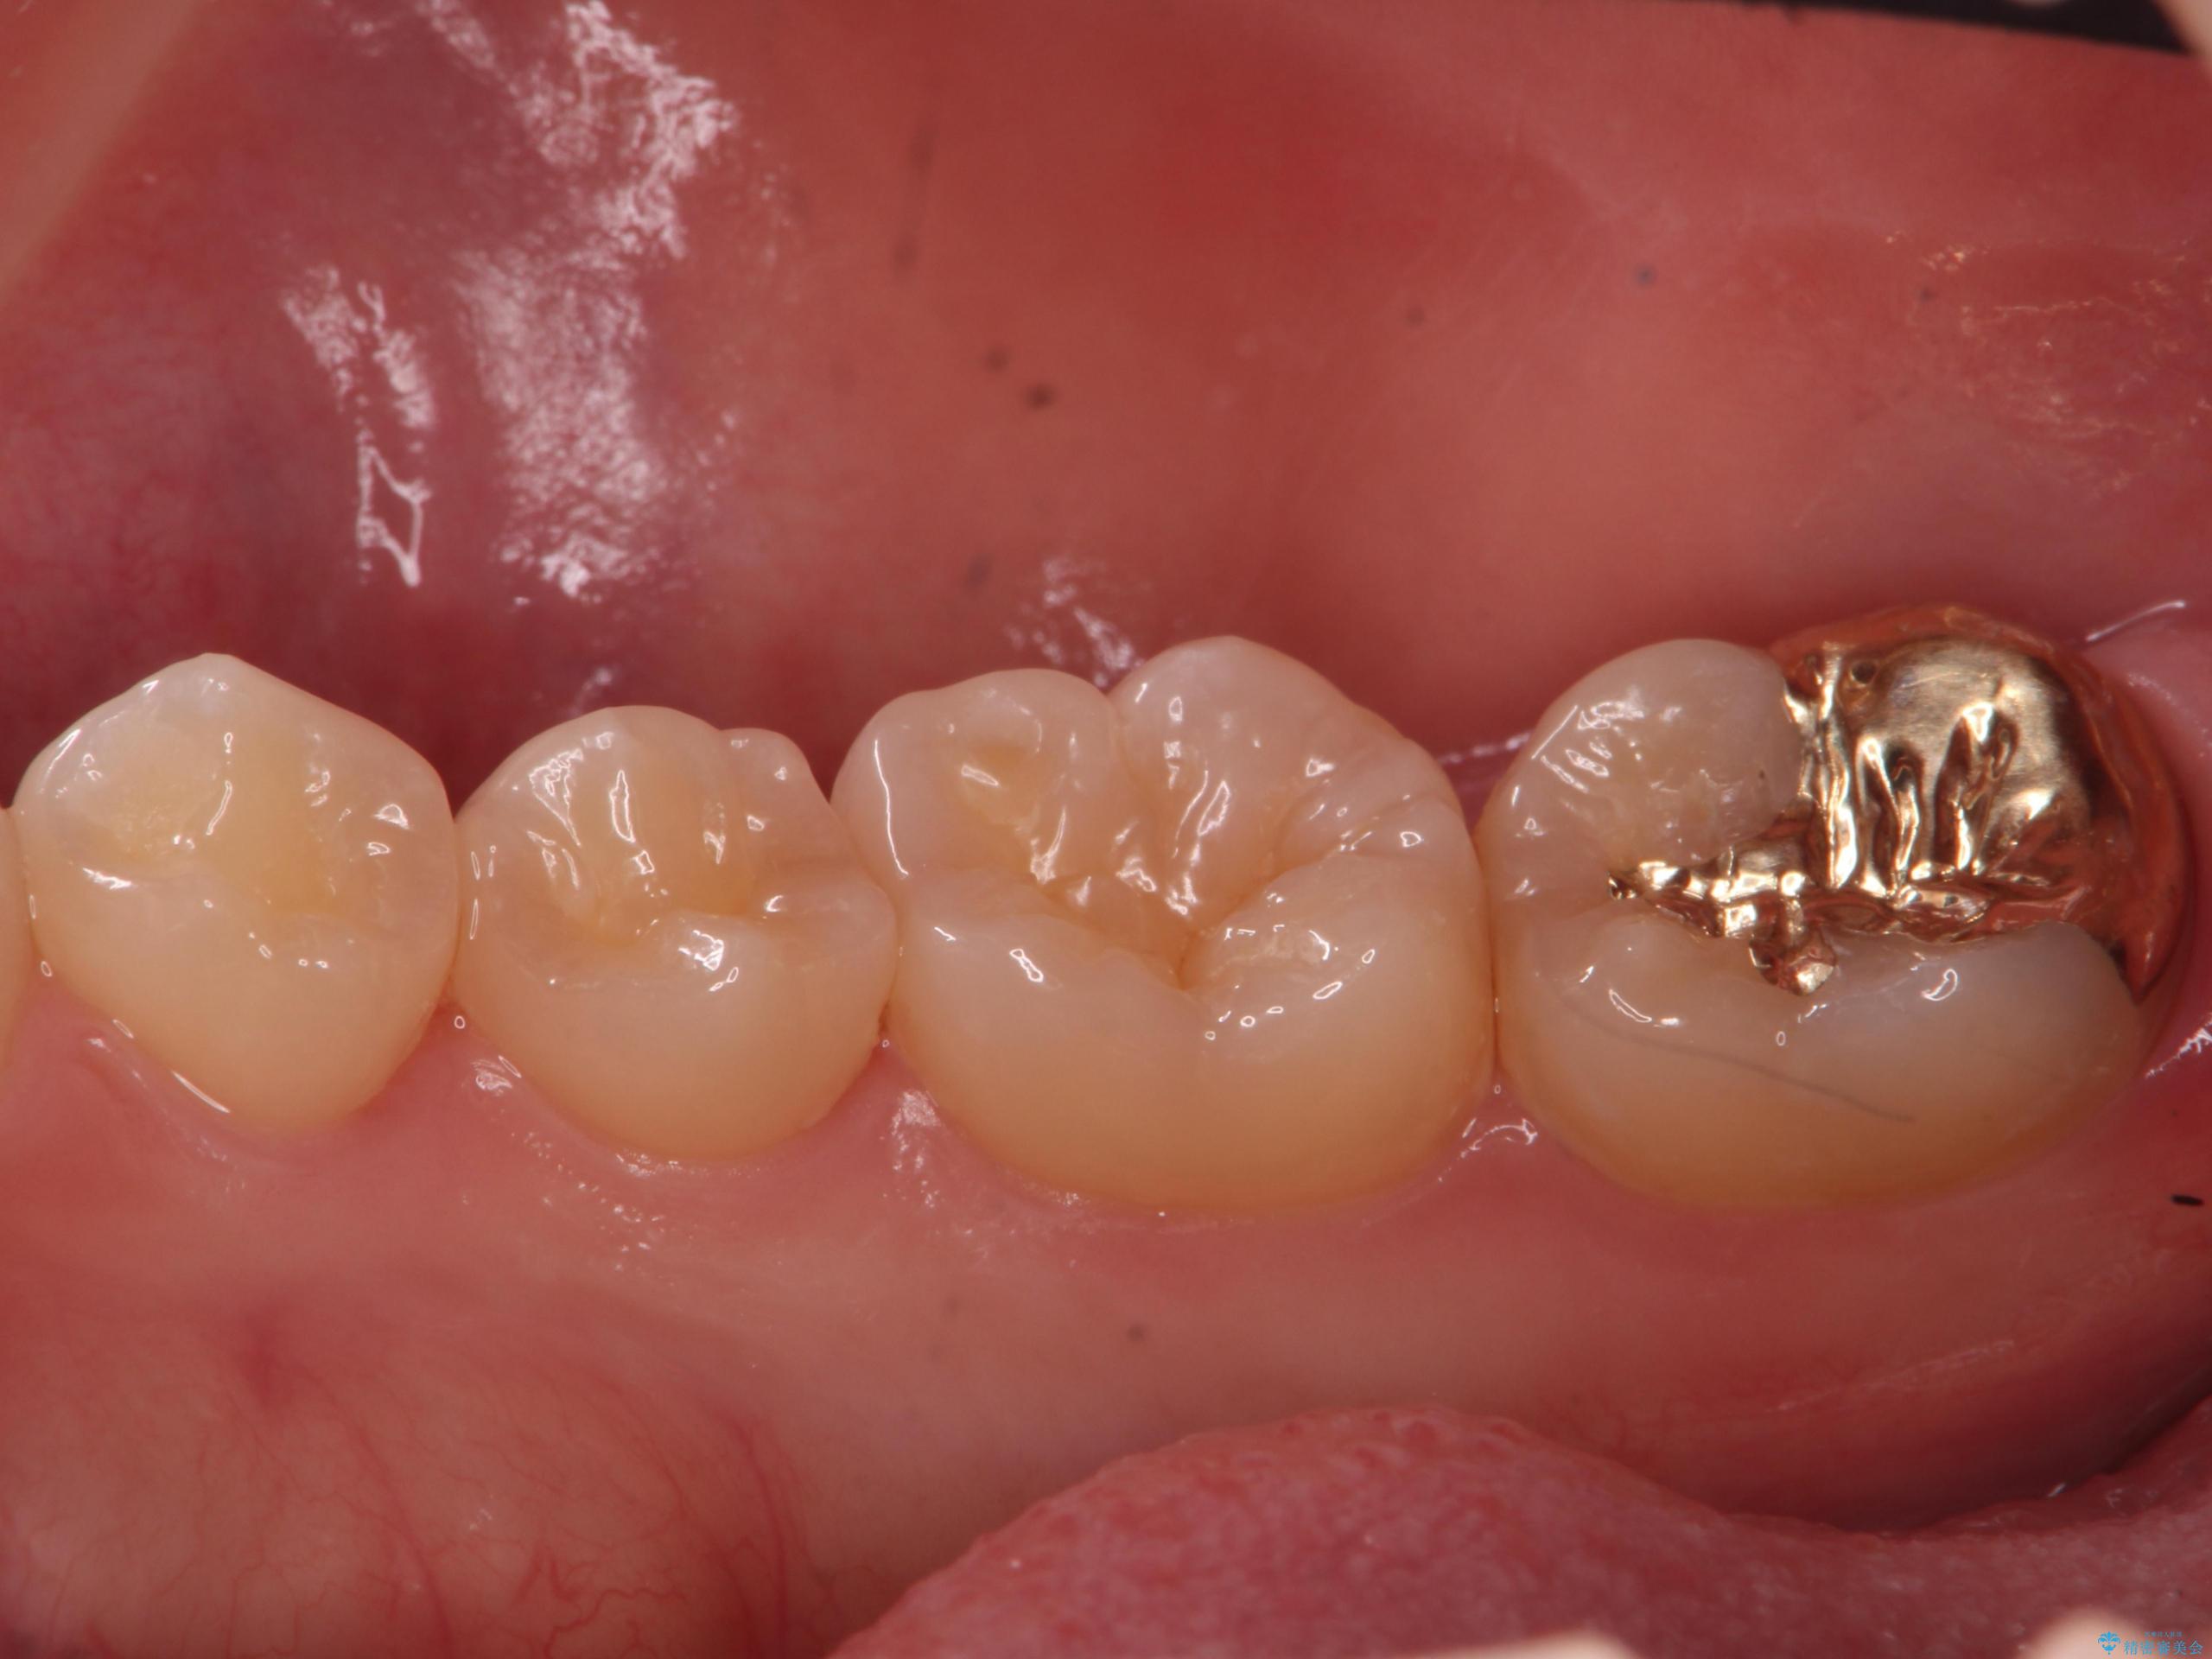

虫歯治療後、精度の良いゴールドアンレーへ

比較的大きな虫歯でしたがゴールドでの修復にすることで歯の削る量を抑え、精度の高い治療を行うことができました。

親知らずの問題も同時に解決することで今後の虫歯リスクを抑えています。